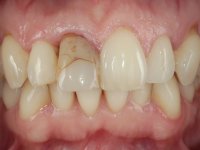

The patient did not like the upper right central incisor. I wanted to improve the smile because the “front tooth was dark and narrow”.

Female patient, 41 years old, non-smoker. It presented tooth 11 with a composite resin restoration, of great extension, very infiltrated and aesthetically poor. In the imaging exam, it was verified that the endodontic treatment was not technically satisfactory, but asymptomatic for almost 20 years. Between teeth 11 and 12 it showed a periodontal pocket certainly related to the non-adapted restoration. Tooth 11 showed a reduced mesiodistal diameter in relation to the symmetrical one. Medium thickness periodontal with satisfactory oral hygiene.

The treatment began with the placement of an intraradicular post and the creation of a new composite resin restoration. This procedure was performed with a surgical approach that allowed the remaining margins to be completely exposed, which were shown to be at a very infra-gingival level. Simultaneously, the periodontal pocket was curetted and root scaling and root planning of adjacent teeth were performed. Two months after this first intervention, the making of the crown began. A pre-print on silicone was performed to make a temporary crown with dual-cured composite resin. Gingival retraction was performed using the technique of kaolin paste compressed by the provisional crown. The impression was made using the double-mix technique with double viscosity with quick-setting silicone. In the laboratory, a crown with a ceramic-coated Zr infrastructure was made. The crown slightly overlapped tooth 12, allowing a dimensionally mimicry of the symmetrical tooth. Its fit was confirmed and approved by the patient; it was definitively cemented with resin-reinforced glass ionomer cement.